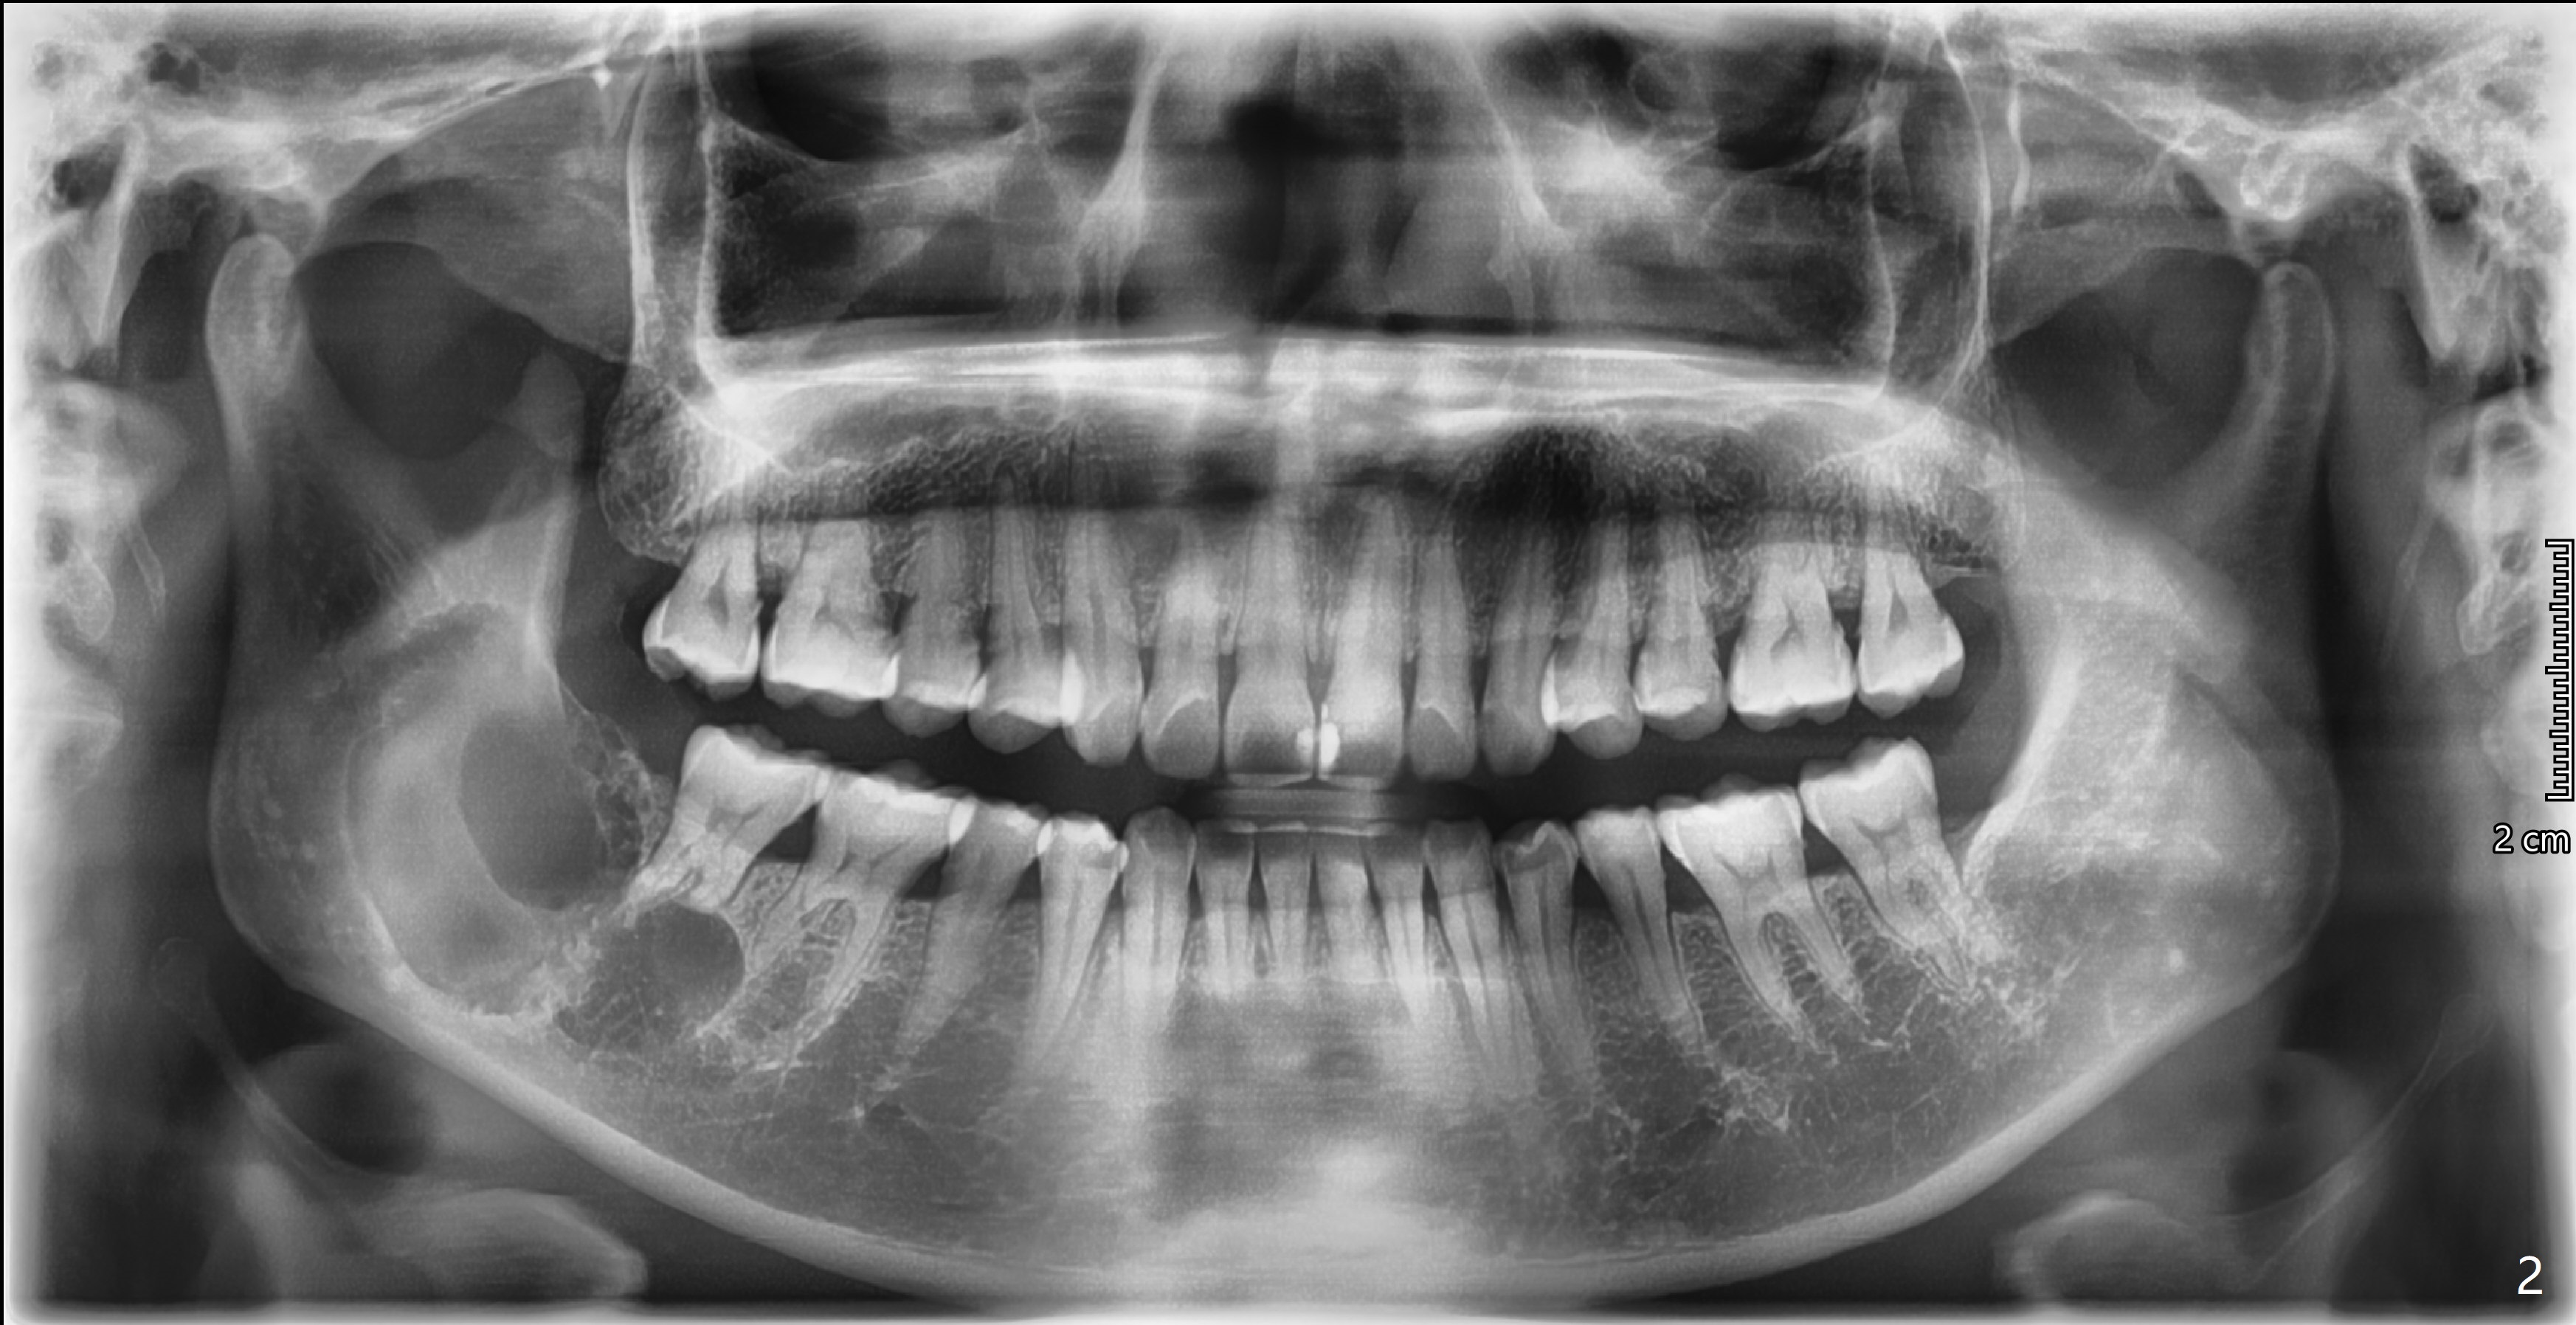

看多房阴影  上方牙槽骨内多个小房(?)  7近中根尖吸收  造釉细胞瘤可能性大

神经应被压迫在颌骨下缘  这X线片上看不到  要看断层  这病例陈平兄是专家

我在日本大学口外20年 清楚他们的治疗方法  这病例还有舌侧骨壁吸收?  向升枝上方浸润(?)  边界不清  也是造釉细胞瘤的特征  记得国内  以前为彻底根治  防止复发 选择截骨方法  在日本  看到相似病例  选择保留颌骨的治疗  看这病例  虽骨吸收区大  但仍有相当骨组织存在 做术中快速切片确诊  切开翻瓣  彻底刮扒干净后 用大圆钻头  尽可能磨除肿瘤区浅层骨面  如需要  用金属板在颊侧下缘固定防骨折(这病例好像不需要)  置皮片引流  缝合关闭  争取I期愈合  关键是术后隔3月  6月  X线复查  如有骨吸收复发  再次做局部手术去除肿瘤组织  这样不截骨  成功可能性较大  当然  最后不能控制  还是要截骨  定期复查是关键  期待听到口外专家的高见[Trick][Trick]

Yaoli @xin wei 下7已受波及  周围骨组织和近中根尖吸收  应拔除  下6好像不在肿瘤骨吸收区内  可保留  术后定期牙片复查  供你参考[Trick][Trick]